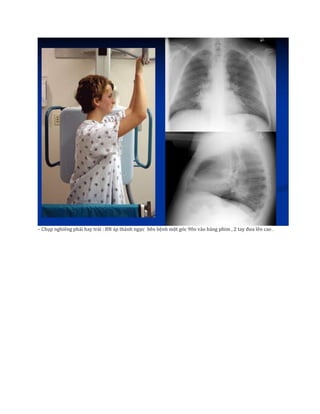

– Chụp nghiêng phải hay trái : BN áp thành ngực bên bệnh một góc 90o vào bảng phim , 2 tay đưa lên cao .

– Chụp nghiêngphải hay trái : BN áp thành ngực bên bệnh một góc 90o vào bảng phim , 2 tay đưa lên cao .